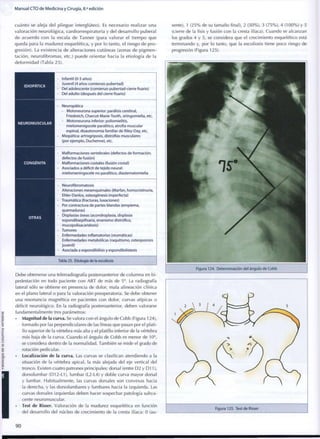

(a) Tratamiento de fractura de olécranon con agujas y cerclaje

(b) Fractura-luxación de Monteggia

Figura 17. Fracturas alrededor del codo